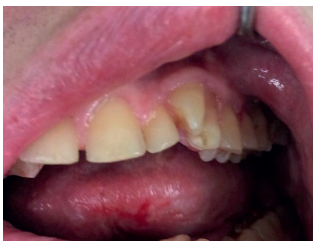

No es frecuente que estos pacientes presenten alteraciones a nivel dentario y gingival como en otros tipos de MPS, pero sí se ha observado una mayor incidencia de bruxismo. Además, pueden presentar dientes supernumerarios con la consiguiente maloclusión que, debido al deterioro del sistema nervioso central desde edades muy tempranas, no puede llevarse a cabo el control por el ortodoncista. En los casos en que, debido a inclusiones dentarias o dientes supernumerarios que provocan patología y se requiere su tratamiento quirúrgico, éste deberá llevarse a cabo bajo sedación25-27 (Figuras 6, 7 y 8).

Los individuos con síndrome de Sanfilippo normalmente tienen los labios más gruesos y una lengua grande. Las encías suelen presentar un alto grado de queratinización, pero debido a la dificultad de la higiene, son susceptibles de patología periodontal. Los dientes están más distanciados, mal formados y con el esmalte frágil, lo que resulta en lesiones cariosas de diferente grado, en prácticamente todas las superficies dentales. Es muy importante tener un buen cuidado dental, ya que las caries pueden causar muchos problemas en su estado general de salud y el dolor puede pasar desapercibido por la falta de comunicación.

Cuando comienzan el recambio dentario, se debe mantener continuas revisiones odontológicas, puesto que en estos casos existen problemas para la exfoliación de los dientes deciduos. Se pueden encontrar dientes supernumerarios e inclusiones dentarias, que serán extraídos por un especialista en quirófano bajo sedación profunda, debido a la alteración cognoscitiva importante que suelen presentar y/o hiperactividad en fases intermitentes39 (Figuras 9, 10 y 11).

En el trabajo publicado sobre alteraciones dentofaciales de Drazewski y cols.41 concluyeron que las dimensiones intermaxilares no fueron estadísticamente diferentes entre los tipos de MPS. Sin embargo, la altura y la longitud de la mandíbula fueron claramente menores en MPS I en comparación con MPS II y MPS III. Esto se asoció con la reabsorción progresiva de los cóndilos mandibulares en MPS I, que también se observó en MPS II y VI, pero no en MPS III o IVa. En cambio, la anchura mandibular fue significativamente menor en los individuos con MPS I, siendo el grupo que presentaba menor bruxismo. Debido a la parafunción, sumado a la hiperactividad de movimientos involuntarios de estos pacientes, se producen fracturas y desgastes de las superficies dentarias que pueden erosionar la mucosa oral, por lo que deben pulirse las superficies afectadas de manera meticulosa y, en casos extremos, convendría realizar la extracción dentaria.